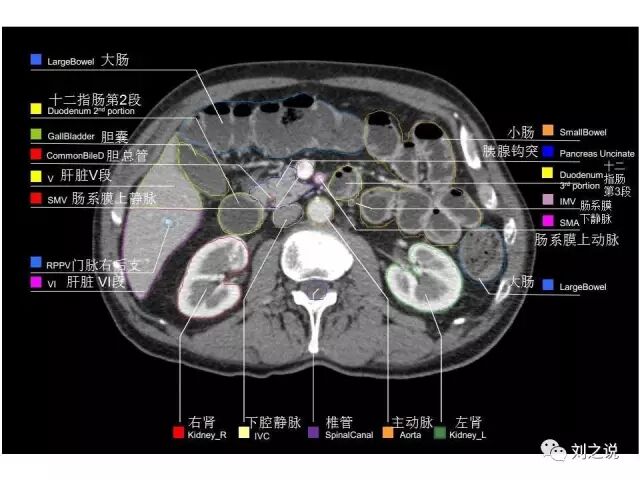

参考RTOG共识和3D-body解剖。

来源:刘之说